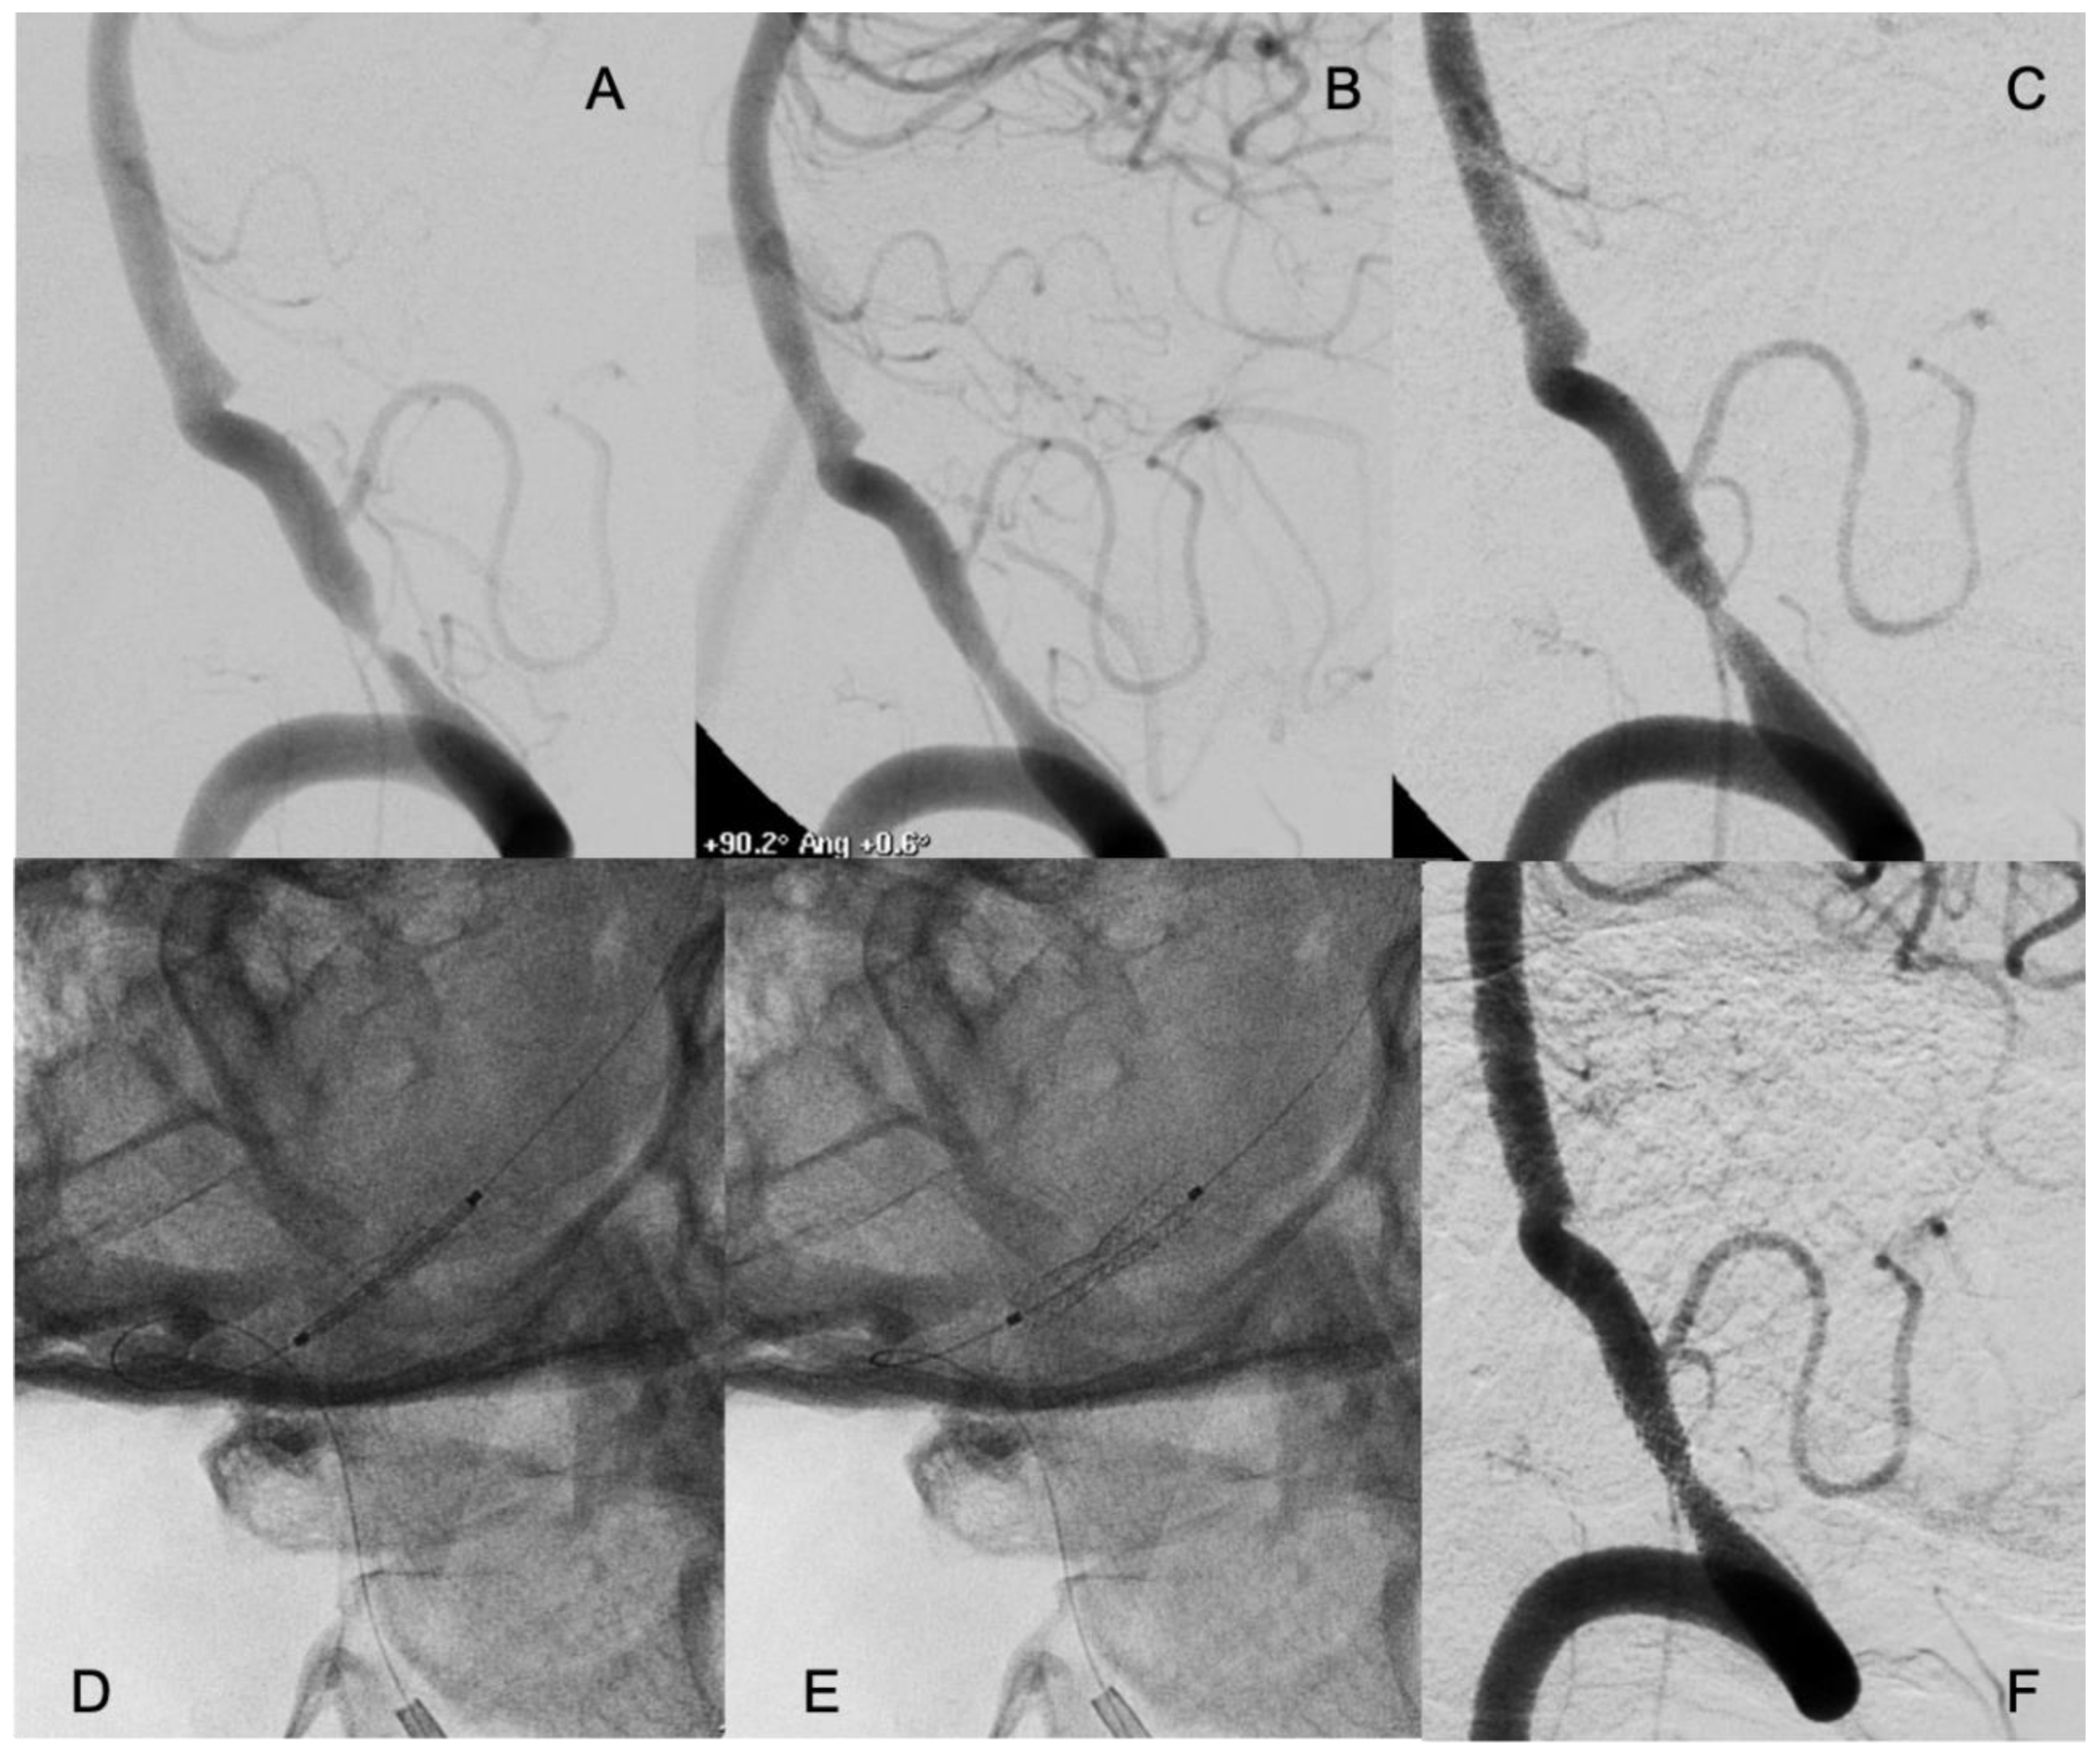

Restenosis (≥50%) at median radiological follow-up of 12 months was observed in 4 patients (11.1%): 2 patients were treated with self-expanding stents, and 2 patients with bare-metal stents). All four patients had symptomatic restenosis. Two of these restenoses required endovascular re-treatment; 1 patient was re-treated with balloon angioplasty, and 1 patient with drug-eluting stent (Figure 2).

Figure 2. A patient who suffered several drop attacks due to a stenosis of the right vertebral artery with concomitant occlusion of the left (A). The patient underwent an endovascular treatment with placement of a coronary balloon expandable stent with resolution of the stenosis and relief of the symptoms (B). 6 months later symptoms relapsed, and an in-stent restenosis was diagnosed (C). An everolimus-eluting coronary balloon expandable stent was placed covering the bare metal previously placed (D and E) with complete resolution of the stenosis. The patient had no new symptoms in the follow-up with persistence of the patency of the treated artery.